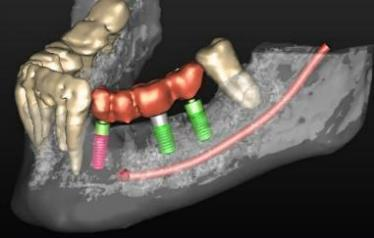

Cone Beam CT

Millions of people world wide have partial or complete edentulism. Dentures do not fully compensate patients adequately for tooth loss cosmetically or functionally. To address these issues dental implants are the accepted alternative. Dentists and oral surgeons will often initially assess their patients with x-ray. Dental CT programs offer more detailed and accurate information providing comprehensive preoperative assessment. Prior to performing this procedure, analysis of the bone of the mandible and maxilla is required in order to plan the appropriate implant procedure and limit surgical complications. The scanner allows for planning of dental implants by reconstructing the area of interest, identifying bone volume and vital nerves that need to be avoided. Excellent modality for bone detail and visualization of inner ear and paranasal sinusses. Low radiation dose especially useful in pediatrics.